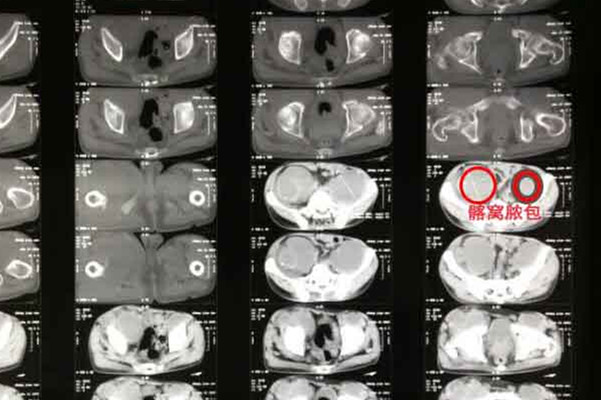

首先为什么会发生骨结核,临床上有多种原因,一种可能是由于结核杆菌直接侵袭到人体的骨质引起病变,还有一种可能是在肺部感染后,通过血液的传播到骨骼系统继而引起骨结核。那么什么是骨结核脓肿呢,顾名思义就是骨质或软组织发生局部坏死,而这个坏死病灶就会在此处出现脓液。这是骨结核较为常见的并发症之一。

目前临床上结核造成的脓肿与我们以往常见的化脓性感染不同,虽然该脓肿多数情况下也会现有有疼痛、肿胀的感觉,但却没有红、热等现象出现,所以骨结核形成的脓肿又称“冷脓肿”或“寒性脓肿”。